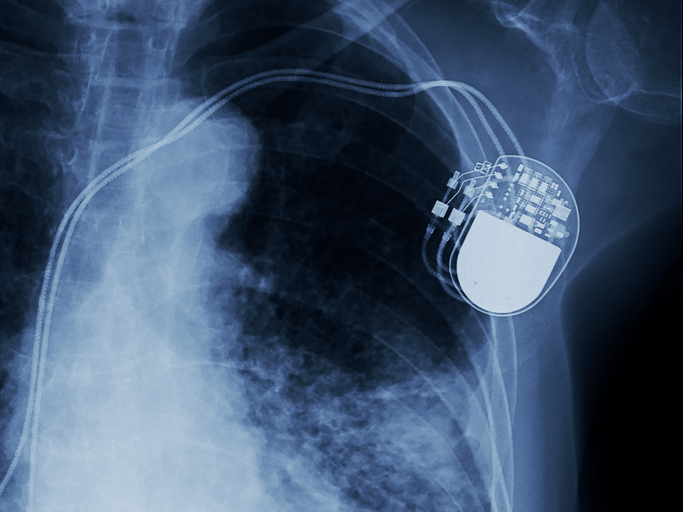

Individuals with cardiac implantable electronic devices have a higher risk of tricuspid regurgitation.

BC survivors undergoing CIED placement have a higher risk of periprocedural complications.

There have been dramatic improvements in remote monitoring among both urban and rural patients with CIED.

For patients with CIEDs who undergo remote monitoring, routine in-person visits may not be needed.

Researchers assessed the safety of rides for patients with cardiac implantable electronic devices.

Frailty significantly increases the risk of both in-hospital mortality, and complications in HFrEF patients following CIED.

Over half of of adolescents with cardiac implantable electronic devices have abnormal health screens.